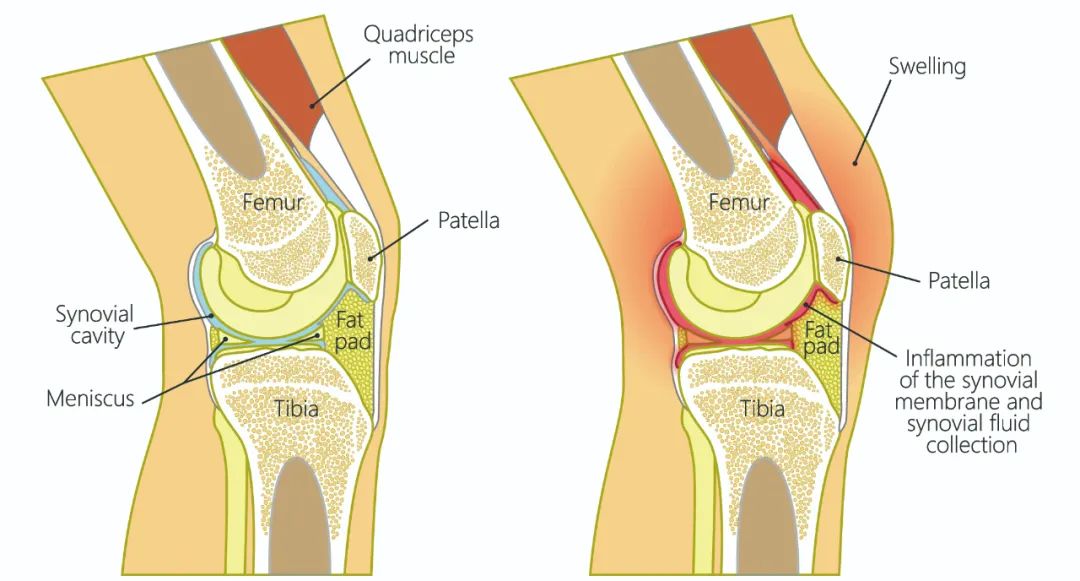

髌骨骨折只占全身骨折的 1%,治疗方式的选择和并发症的防治尤其要注意,急诊来了髌骨骨折患者,你怎么处理?髌骨是人体最大的籽骨,位于膝关节伸膝装置内。解剖特点包括近端宽大的基底和关节外的远侧尖端,前面位于关节外,后面为关节面。股直肌和股中间肌止于髌骨基底部,股内侧肌和股外侧肌止于髌骨的两侧。髌腱起于髌骨尖端,止于胫骨结节。髌骨骨折约占所有骨折的 1%,主要由直接暴力造成,如跌倒时跪地或膝关节屈曲时受到打击。典型的体征包括关节肿胀、压痛、伸膝功能部分或完全丧失。除以主诉和典型体征外,膝关节 X 线片也是必不可少的一项辅助检查,以膝关节正侧位 X 线片最常见,如果怀疑纵向骨折,膝关节屈曲 45° 时髌骨 30° 切位片可以辅助诊断。对于骨折不愈合、畸形愈合所致的关节面不平整以及髌股关节对应关系不良可采用 CT 检查。MRI 有助于诊断软骨缺损和损伤。34-B 型(部分关节内骨折,伸膝装置完整,如纵行骨折)髌骨下极骨折袢钢板结合克氏针、张力带固定 图源:作者提供

术中切开显露髌骨时,最理想的的分离层面为皮下筋膜和伸膝装置之间,如若在皮肤和皮下筋膜之间进行分离,可能会造成伤口边缘坏死。对于开放性髌骨骨折应及时给予清创处理,对于闭合性髌骨术后感染患者应及时进行清创灌洗直至伤口愈合。如有深部感染则推荐长期使用抗生素。透明降解物会产生轻重不等的无菌性滑膜炎,这很难和感染相区分。需行关节镜检查来确定。在进行克氏针固定髌骨时,克氏针的末端应剪短,否则有穿破皮肤以及术后活动时疼痛的风险。髌骨骨折术后内植物至少在损伤后 9 ~ 12 个月才能取出。高密度的骨皮质需要这么长时间才能愈合,从而能在无保护情况下承受高张力。必须防止这一并发症的发生,因为会导致膝关节屈曲严重受限。用环扎钢丝来保护髌腱时,有可能因为错误估计髌腱长度而造成髌骨低位。髌骨的正常位置可以参照健侧膝关节的 X 线片。屈曲受限的患者需要进行强化理疗。如果在数月内运动的范围没有增加,下一步可行关节镜下松解,去除髌上囊的挛缩瘢痕。如果髌骨已切除,则可能出现肌腱断裂的晚期并发症。髌骨软骨面的严重损伤、关节面不平整的继发性损伤以及髌股关节受力的改变,都将导致创伤性关节炎的发生。如果髌骨韧带附着位置太靠前方,会使髌骨下极位置靠后,也将导致创伤性关节炎。在前一种情况下,可以行关节镜下清理;后一种情况下需改变韧带附着点位置。髌骨术后应及时有效地进行膝关节活动锻炼,一般在术后 3 月时膝关节可屈曲 120° 以上,若术后 3 月时膝关节弯曲角度仍然小于 90°,建议进行辅助康复训练,必要时以手术松解。